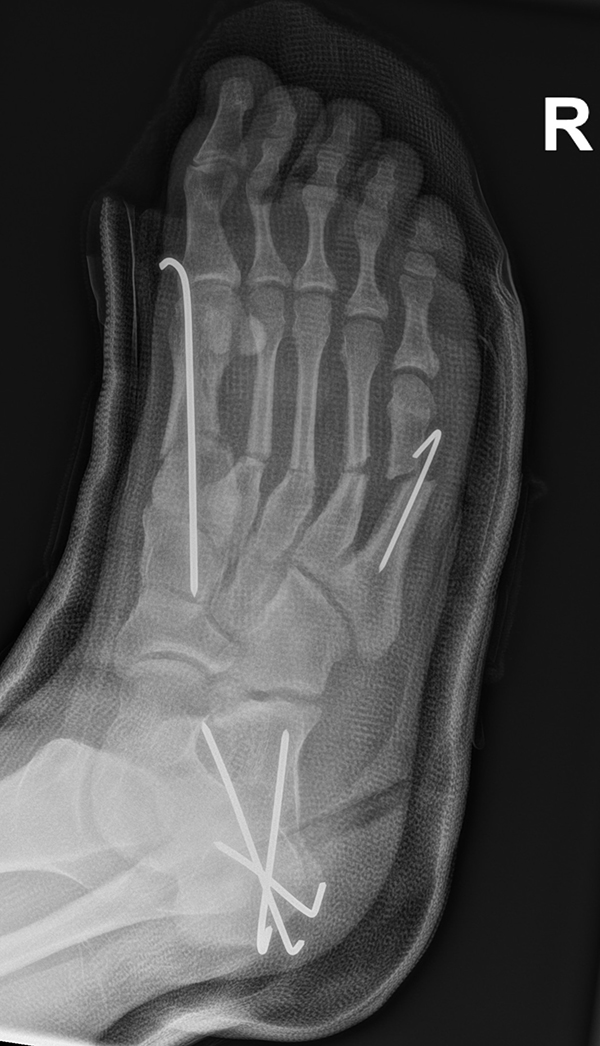

Abb. 36 a-b: Röntgenbild mit allen zuvor beschriebenen Osteotomien und der zusätzlich durchgeführten Metatarsale V Osteotomie in d. p. (dorso-plantare) Ansicht und schräge Röntgenaufnahme.

Zum Lesen der Bildbeschreibung und zur Vollansicht bitte die Bilder anklicken. Bilder: A. Helmers.